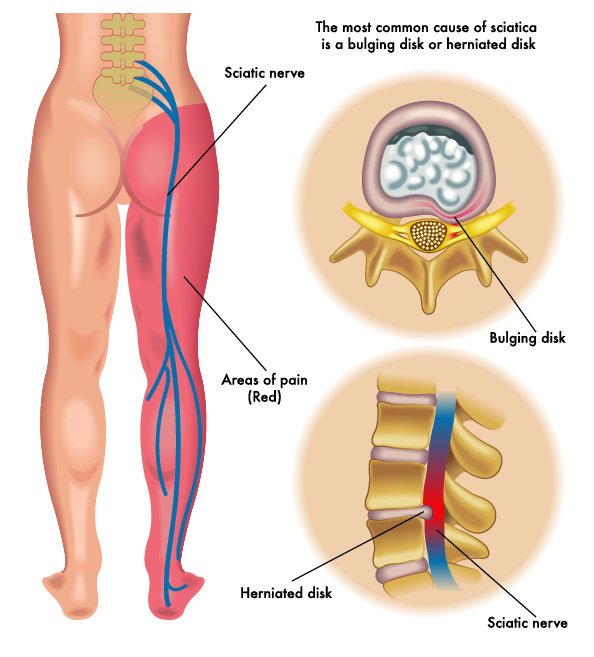

#Spinaldisc pathology can cause leg and/or #backpain -if you're suffering call us for a consultation 0207 935 4750

Do you suffer from sharp pains every time you bend? Back pain, of this nature, is often the result of a #herniateddisc or #pinchednerve: both caused by preventable #spinaldisc problems. Before considering drugs/surgery, a chiropractor can help! Book your appointment today!

A #slipdisc occurs when a #spinaldisc bulges out, causing pain, #numbness, or #weakness. Early #treatment can prevent worsening #symptoms. Dr.SrinivasBotla Neurosurgeon and Spine Surgeon YashodaHospitals,Malakpet For More Visit: srideviclinic.com

A #slipdisc occurs when a #spinaldisc bulges out, causing pain, #numbness, or #weakness. Early #treatment can prevent worsening #symptoms. Dr.SrinivasBotla Neurosurgeon and Spine Surgeon YashodaHospitals,Malakpet For More Visit: srideviclinic.com

As we age, our spinal discs degenerate, which may cause the disc to lose its height or bulge out—potentially compressing a nerve, causing pain or other symptoms. Learn more about spinal discs at rediscovermylife.org/anatomy.php. #rediscover #centinelspine #spinaldisc #discbulge

Treating A Degenerated Spinal Disc Symptoms of degenerative disc disease include pain, paresthesia, and weakness. Spinal fusion surgery is used when symptoms worsen. #spinaldisc #degeneration #mvscburnsville zurl.co/hr68

Herniated disc, bulging disc ... what's the difference? Here's a list of these common terms and what they really mean #spinaldisc #discpain #spinalhealth bit.ly/2sncRjj